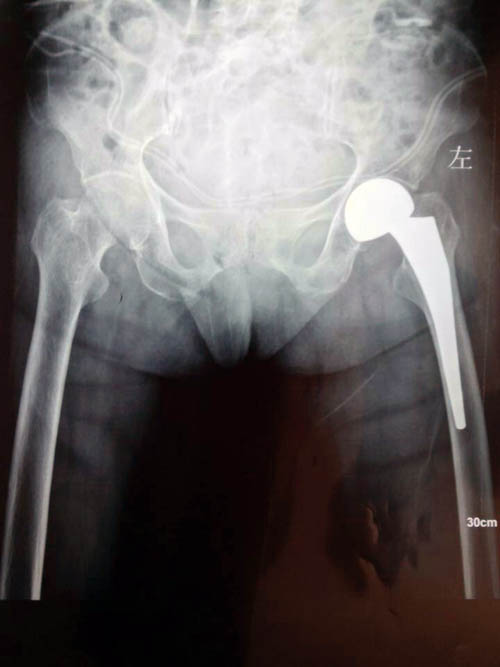

术后摄片

5月6日,郑老太不慎摔伤,经急诊收治入院,转到骨二科后,由周立义博士主管,在经管医师李晨、何剑影的共同配合下,老人家被确诊为左侧股骨骨折(头下型),完善相关术前检查后,经科室讨论,认为如此高龄的老人要进行手术需请麻醉科张明生主任、钟文胜副主任前来进行评估,二位主任来到病房与郑老太进行了访谈沟通,对其病情进行了评估。5月10日,在周立义博士的主刀下,顺利完成全麻下左侧股骨颈骨骨折人工股骨头假体置换术,术中患者生命体征平稳,术后康复治疗恢复良好,已经拆线出院。